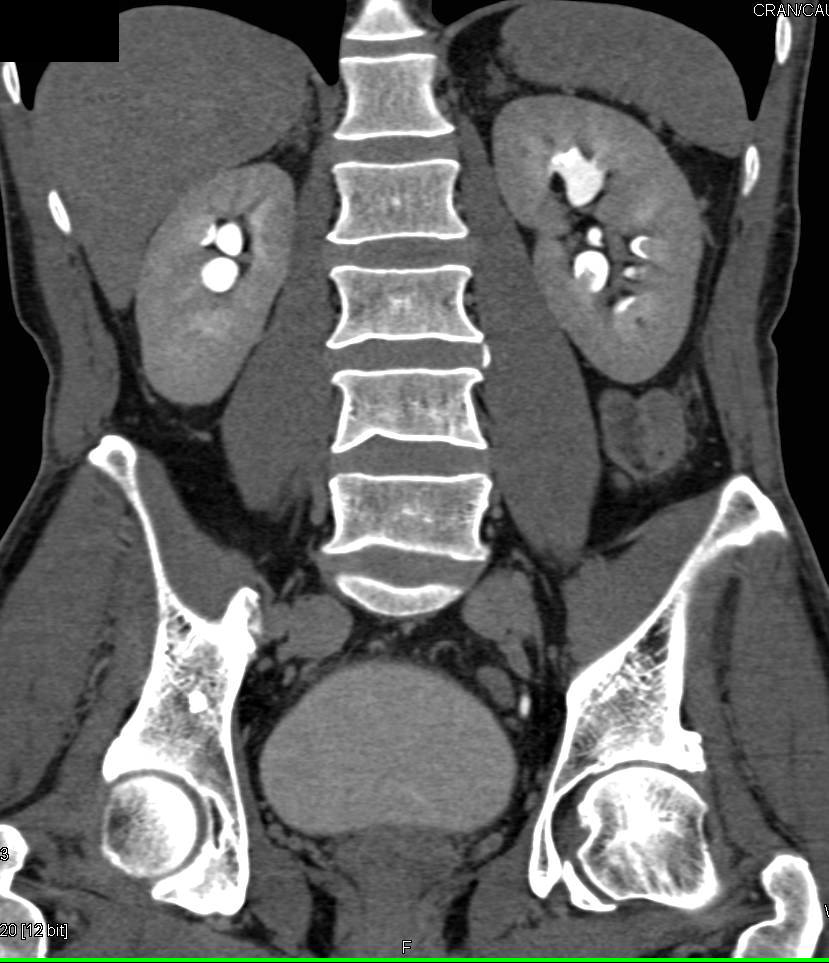

A middle-aged female patient presented with acute onset, severe, colicky left flank pain radiating to the groin for four days. There was no associated history of fever, gross hematuria.Pre-operative CT Kidney Ureter Bladder with contrast revealed right ureteric and left renal calculi.On admission, vital signs were stable: Physical examination was unremarkable, with a soft, non-tender abdomen and normal bowel sounds. The patient remained hemodynamically stable throughout the initial evaluation.

Relevant Test Results Prior to Catheterization

Initial laboratory work-up showed normal renal function (details of specific values withheld for privacy/length). Imaging confirmed the diagnosis of right ureteric calculus and left renal calculus, which was the target of the initial intervention. The left kidney appeared hydronephrotic due to the obstruction.